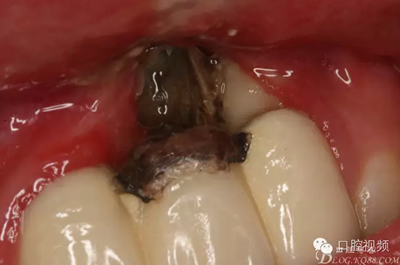

【原創(chuàng)博客】烤瓷橋下的悲劇-張東星